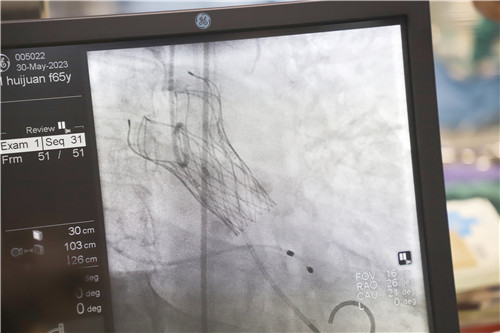

為保證創(chuàng)傷小、恢復(fù)快、并發(fā)癥可控,心血管內(nèi)科聯(lián)合麻醉科、醫(yī)學(xué)影像科、超聲醫(yī)學(xué)科等多學(xué)科會診,反復(fù)溝通討論,最終決定施行TAVR手術(shù),并征得王女士及家人的同意。該項微創(chuàng)介入技術(shù)對術(shù)者的技能操作水平和醫(yī)院的綜合救治能力要求極高,從大腿股動脈置入導(dǎo)管,再通過導(dǎo)管將人工生物心臟瓣膜輸送至已經(jīng)病變狹窄的瓣膜位置,取代其瓣膜功能。

不為良相,便為良醫(yī)。石化醫(yī)院心血管內(nèi)科團隊在汪念東副院長的帶領(lǐng)下和皖南醫(yī)學(xué)院弋磯山醫(yī)院湯圣興教授的指導(dǎo)下,術(shù)中利用豬尾管懸吊AL1導(dǎo)管增強同軸跟進,經(jīng)過多學(xué)科四個小時的緊張救治,最終建立軌道成功置換瓣膜。

王女士術(shù)前測壓力階差高達(dá)110mmHg,在置換瓣膜后,壓力階差恢復(fù)到5mmHg,且無瓣周漏,在麻醉蘇醒后恢復(fù)了自主心率和自主呼吸。